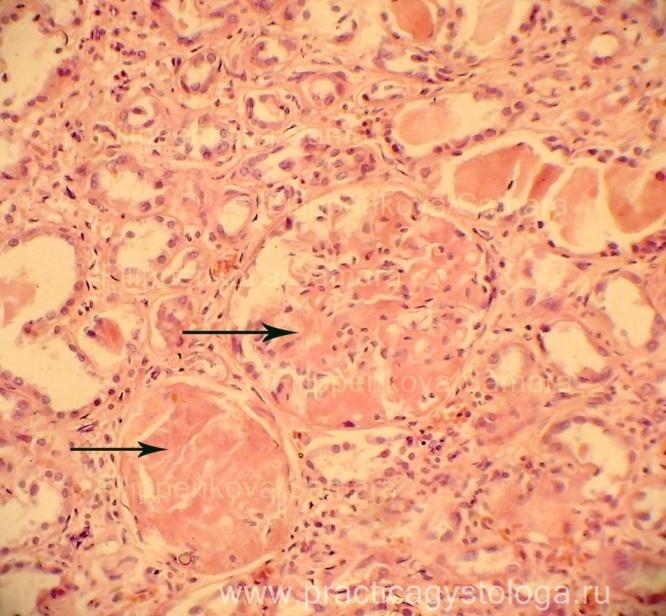

Механизм остро го диффузного гломерулонефрита